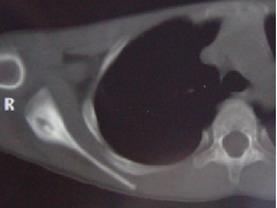

问题 患者,男,34岁,6个月前劳累后出现右肩部疼痛不适,休息后可缓解,曾服用消炎药,对症治疗,效果不佳,实验室检查正常,请结合所提供的图像,选择最佳选项 ( )

选项 A、良性骨母细胞瘤 B、骨样骨瘤 C、骨梅毒 D、骨髓炎 E、右股骨骨纤维异常增殖症

答案 B